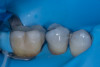

Case 2: Composite Facing Fracture

This case involved a patient with generalized mild anterior wear and an existing composite restoration on the maxillary left central incisor. The restoration extended from the middle third to the incisal edge and had excellent shade match and no marginal discoloration. The patient presented with a fractured central mesial portion of the composite (Figure 14 through Figure 16). Examination revealed a mixed failure pattern: Some adhesive and composite remnants remained on the tooth surface, while the fractured piece showed no residue internally. This finding suggested that the weak point was at the interface between composite and adhesive layer, with a minor cohesive component within the composite itself (Figure 17).

(14.) Intraoral view showing the fractured ceramic fragment positioned in place. The piece fits well, although minor gaps are present between the margins due to slight material loss, which can be restored using luting composite.

Figure 14

(15.) Intraoral view showing the fractured ceramic fragment positioned in place. The piece fits well, although minor gaps are present between the margins due to slight material loss, which can be restored using luting composite.

Figure 15

(16.) Intraoral view showing the fractured ceramic fragment positioned in place. The piece fits well, although minor gaps are present between the margins due to slight material loss, which can be restored using luting composite.

Figure 16